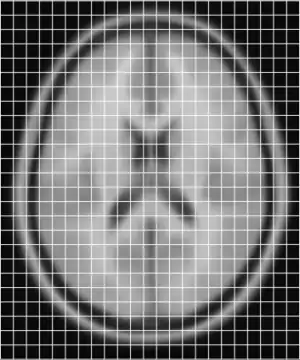

To get an idea of how they currently overlay I have put them together below

Clearly they are not aligned or "registered" to each other so we have to use a tool such as minctracc or mritoself in order to align them as such: